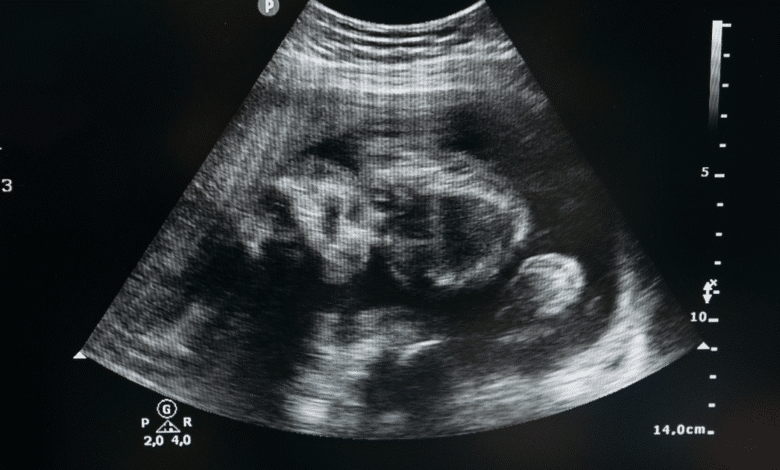

El Congreso del Estado de Chiapas aprobó este miércoles la ley de interrupción legal del embarazo para niñas y adolescentes víctimas de violación, marcando un avance significativo en materia de derechos humanos y salud reproductiva en la entidad.

El nuevo ordenamiento tiene como objetivo regular y garantizar el acceso seguro, gratuito y de calidad a los servicios de interrupción del embarazo en instituciones del sistema estatal de salud, siempre bajo los principios de dignidad humana, perspectiva de género y no criminalización.

Durante la sesión legislativa, se subrayó que el embarazo infantil “no es una elección, sino la consecuencia de un delito”, por lo que la medida busca salvaguardar el interés superior de la niñez y ofrecer acompañamiento médico y psicológico a las menores afectadas.